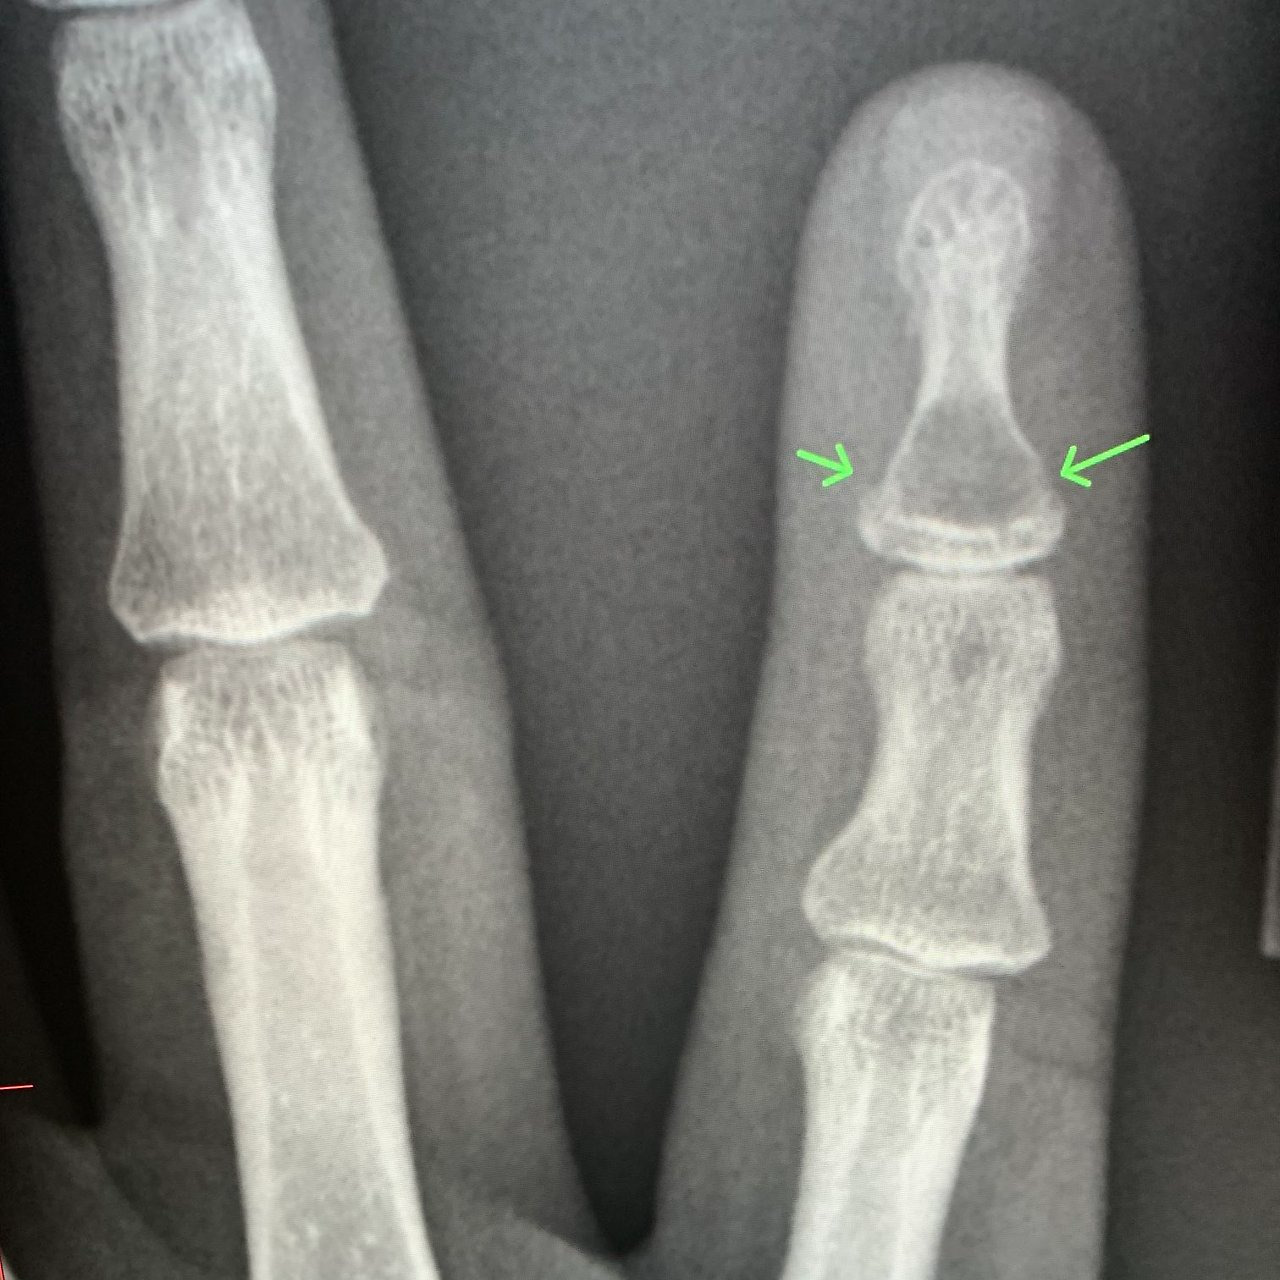

손가락 골절은 기저부(base) 골절, 중간부(shaft) 골절, 관절면(intra-articular) 골절 등으로 나뉘며, 특히 관절면을 침범한 골절은 기능적 후유증이 남을 위험이 높습니다. 따라서 엑스레이 검사로 정확한 위치와 손상 정도를 파악하고, 필요 시 CT나 초음파로 인대 손상 여부를 함께 확인해야 합니다.

손가락에 금이 갔을 때 중요한 것은 정확한 진단입니다. 단순히 통증이 있다고 해서 자가진단으로 테이핑만 하는 것은 위험하며, 반드시 엑스레이 검사를 통해 뼈의 정렬 상태와 골절선을 확인해야 합니다.